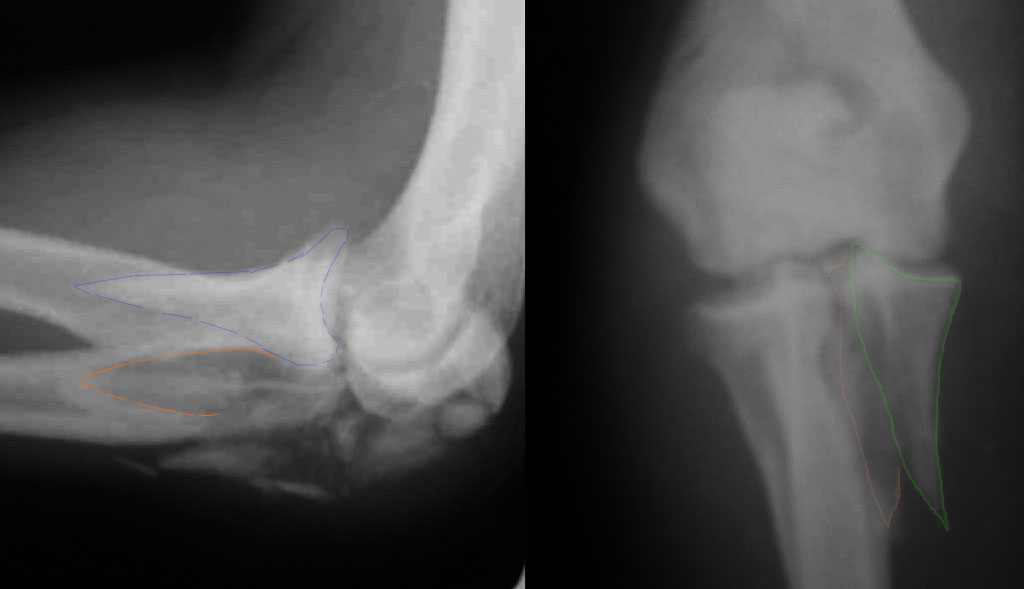

При самом большом к Вам уважении, Сергей Анатольевич, не соглашусь. У меня, после того, как добавили "прямой" снимок, сомнений не осталось. Венечный сломан наверняка. Но чтобы судить, насколько это критично для стабильности, нужно иметь строго боковую проекцию. И при этом помнить, что на него крепятся медиальные связки.

Прикрепляю снимок, где обведен фрагмент, несущий на себе венечный отросток (весь он смещён с этим фрагментом или частично - без качественной боковой проекции судить сложно), и отдельно на снимке обведено "ложе", от которого он сместился.